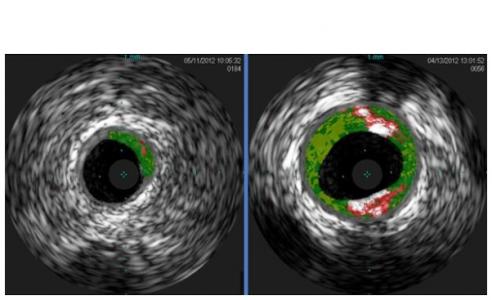

Cette équipe de l'Université de Virginie soutenue par le NIH/National Heart, Lung and Blood Institute révèle la responsabilité de l’allergène de la viande rouge dans le risque associé de maladie cardiaque : certains patients « moins sensibles » à un allergène de la viande rouge présentent une accumulation réduite de plaque dans les artères du cœur (visuel de gauche). Des données présentées dans la revue Arteriosclerosis, Thrombosis and Vascular Biology certes préliminaires mais qui ouvrent une nouvelle approche ou cible potentielle pour prévenir ou traiter les maladies cardiaques dans un sous-groupe de personnes plus sensibles.

Un type d'anticorps (immunoglobuline ou IgE) spécifique de l'allergène alpha-Gal : pour identifier ce marqueur sanguin, les chercheurs ont analysé des échantillons de sang de 118 adultes puis détecté des anticorps dirigés contre l'alpha-Gal, indiquant une sensibilité à la viande rouge, dans 26% d'entre eux. En utilisant l'imagerie, ils constatent que la quantité de plaque est 30% plus élevée chez les patients sensibilisés à l’alpha-Gal que chez les patients non sensibilisés. Ces plaques, caractéristiques de l'athérosclérose (durcissement des artères), ont également tendance à être plus structurellement instables, ce qui suggère un risque accru d’événement cardiaque.